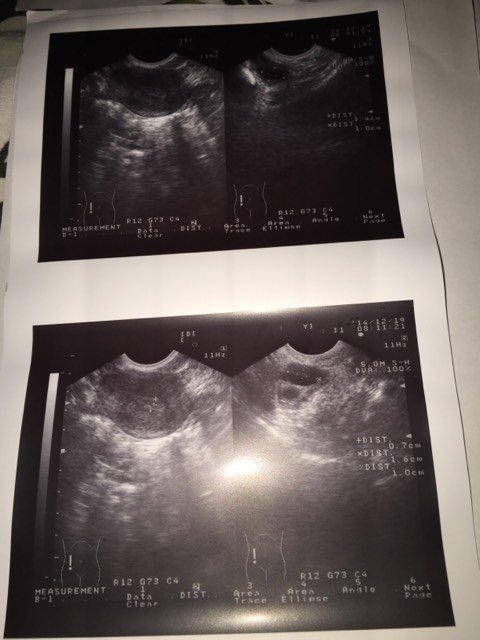

本月姨妈是12/11~12/15,14号开始监测卵泡,医生配了麒麟丸让早晚吃,法地兰一天一次,总共5次,今天监测卵泡,右侧卵泡16*10,左侧14*10,医生开了两针尿促,请问像我这种情况大约多久会排?看我监测的卵泡情况是属于长的快还是慢的,谢谢!

这个有用促排药物了,就可以在等看结果的,你15号月经干净的,才开始进入排卵期的,卵泡发育的还可以的,所以可以用药物后,过2天在检测一次,应该是就要排了,有长大的情况,就及时的准备同房了,防止有错过排卵的情况,发育的还可以的,在观察一下的。